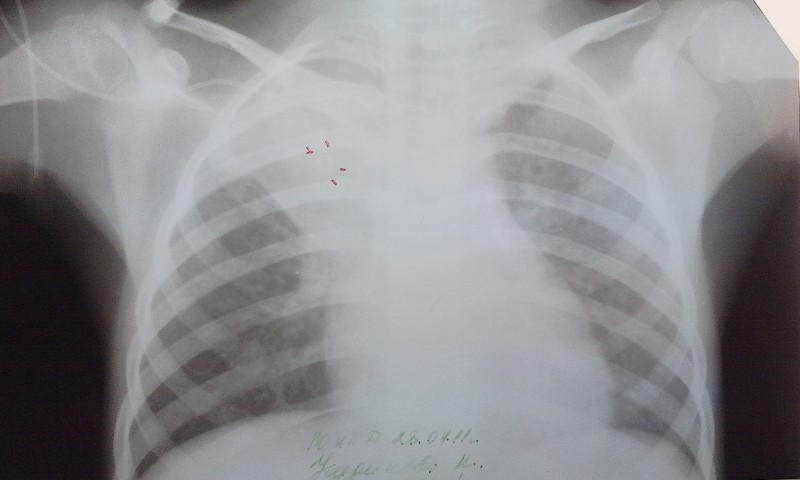

Изначально был выделен самостоятельный курс по преподаванию туберкулёза, позднее преобразованный в кафедру, Г.Я. Цукерман не только возглавил курс, но и руководил процессом его трансформации в полноценную кафедру фтизиопульмонологии, под его руководством проводились исследования состояния сердечно‑сосудистой системы при туберкулёзе (совместно с А.А. Бириным, Ю.И. Колесовым, Э.Н. Шмелёвым).

По разделу научной работы на кафедре проведены исследования по вопросам первичного туберкулёза, его клиники, иммунологии и иммуногенетики (А.С.Борзенко). Изучено состояние сердечно-сосудистой системы при туберкулёзе (Г.Я.Цукерман, А.А.Бирин, Ю.И.Колесов, Э.Н.Шмелёв). Проблеме лечения туберкулёза посвящены работы К.В.Карадуты и И.М.Таипова, вопросам микробиологических и иммунологических исследований работы В.Ю.Перова, Н.Л.Попковой, Э.Б.Белан. Проблеме лекарственно-устойчивого туберкулеза работа С.Г. Гагариной, проблеме реабилитации больных туберкулезом впервые признанных инвалидами работа А.А. Калужениной. На основе проведенных данных исследований были защищены диссертации.